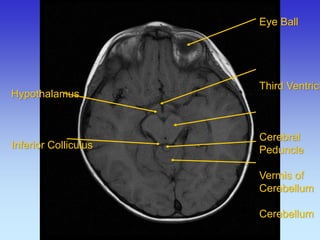

Eye Ball Third Ventricle Cerebral Peduncle Vermis of Cerebellum Cerebellum

Hypothalamus Inferior Colliculus

Third Ventricle Superior colliculus Cerebellum